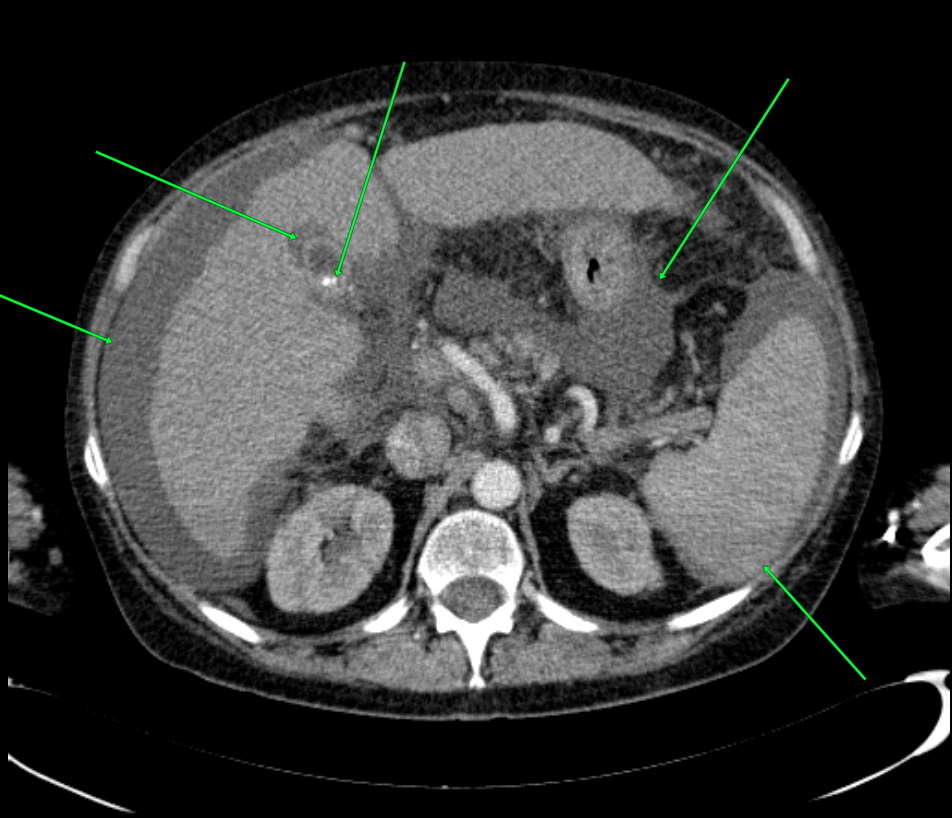

КТ-исследование абсцесса малого таза: Визуализация и диагностика

Раздел: Фотоальбом решений